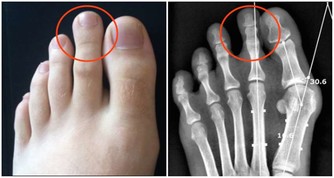

「環軸關節」在哪裡?有憂鬱傾向的人這會痛。 「環軸關節」是指頭部和頸部接合處的關節,

位在第一頸椎和第二頸椎之間;其反射區在腳姆趾趾腹上方1/3的橫切線。

對應部位1/環軸關節(1點按壓)

刺激姆趾腹前段「環軸關節」的反射區,

棉花棒垂直握拿,朝趾尖方嚮往上按壓;慢慢地往橫向點按。